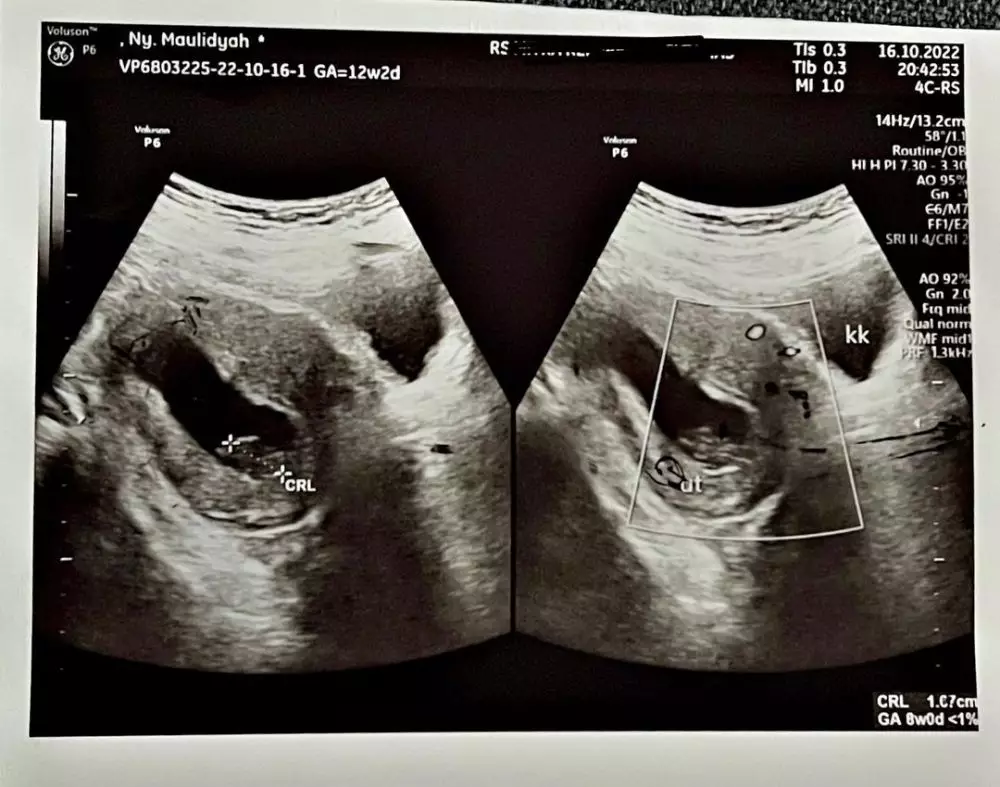

Melansir dari Instagram @viavallen, Rabu (26/10), dokter mengatakan janin berhenti berkembang di usia 8 minggu, yang seharusnya saat itu janin sudah di usia 12 minggu. Janin yang ada di perut Via sudah tak berkembang selama 1 bulan.